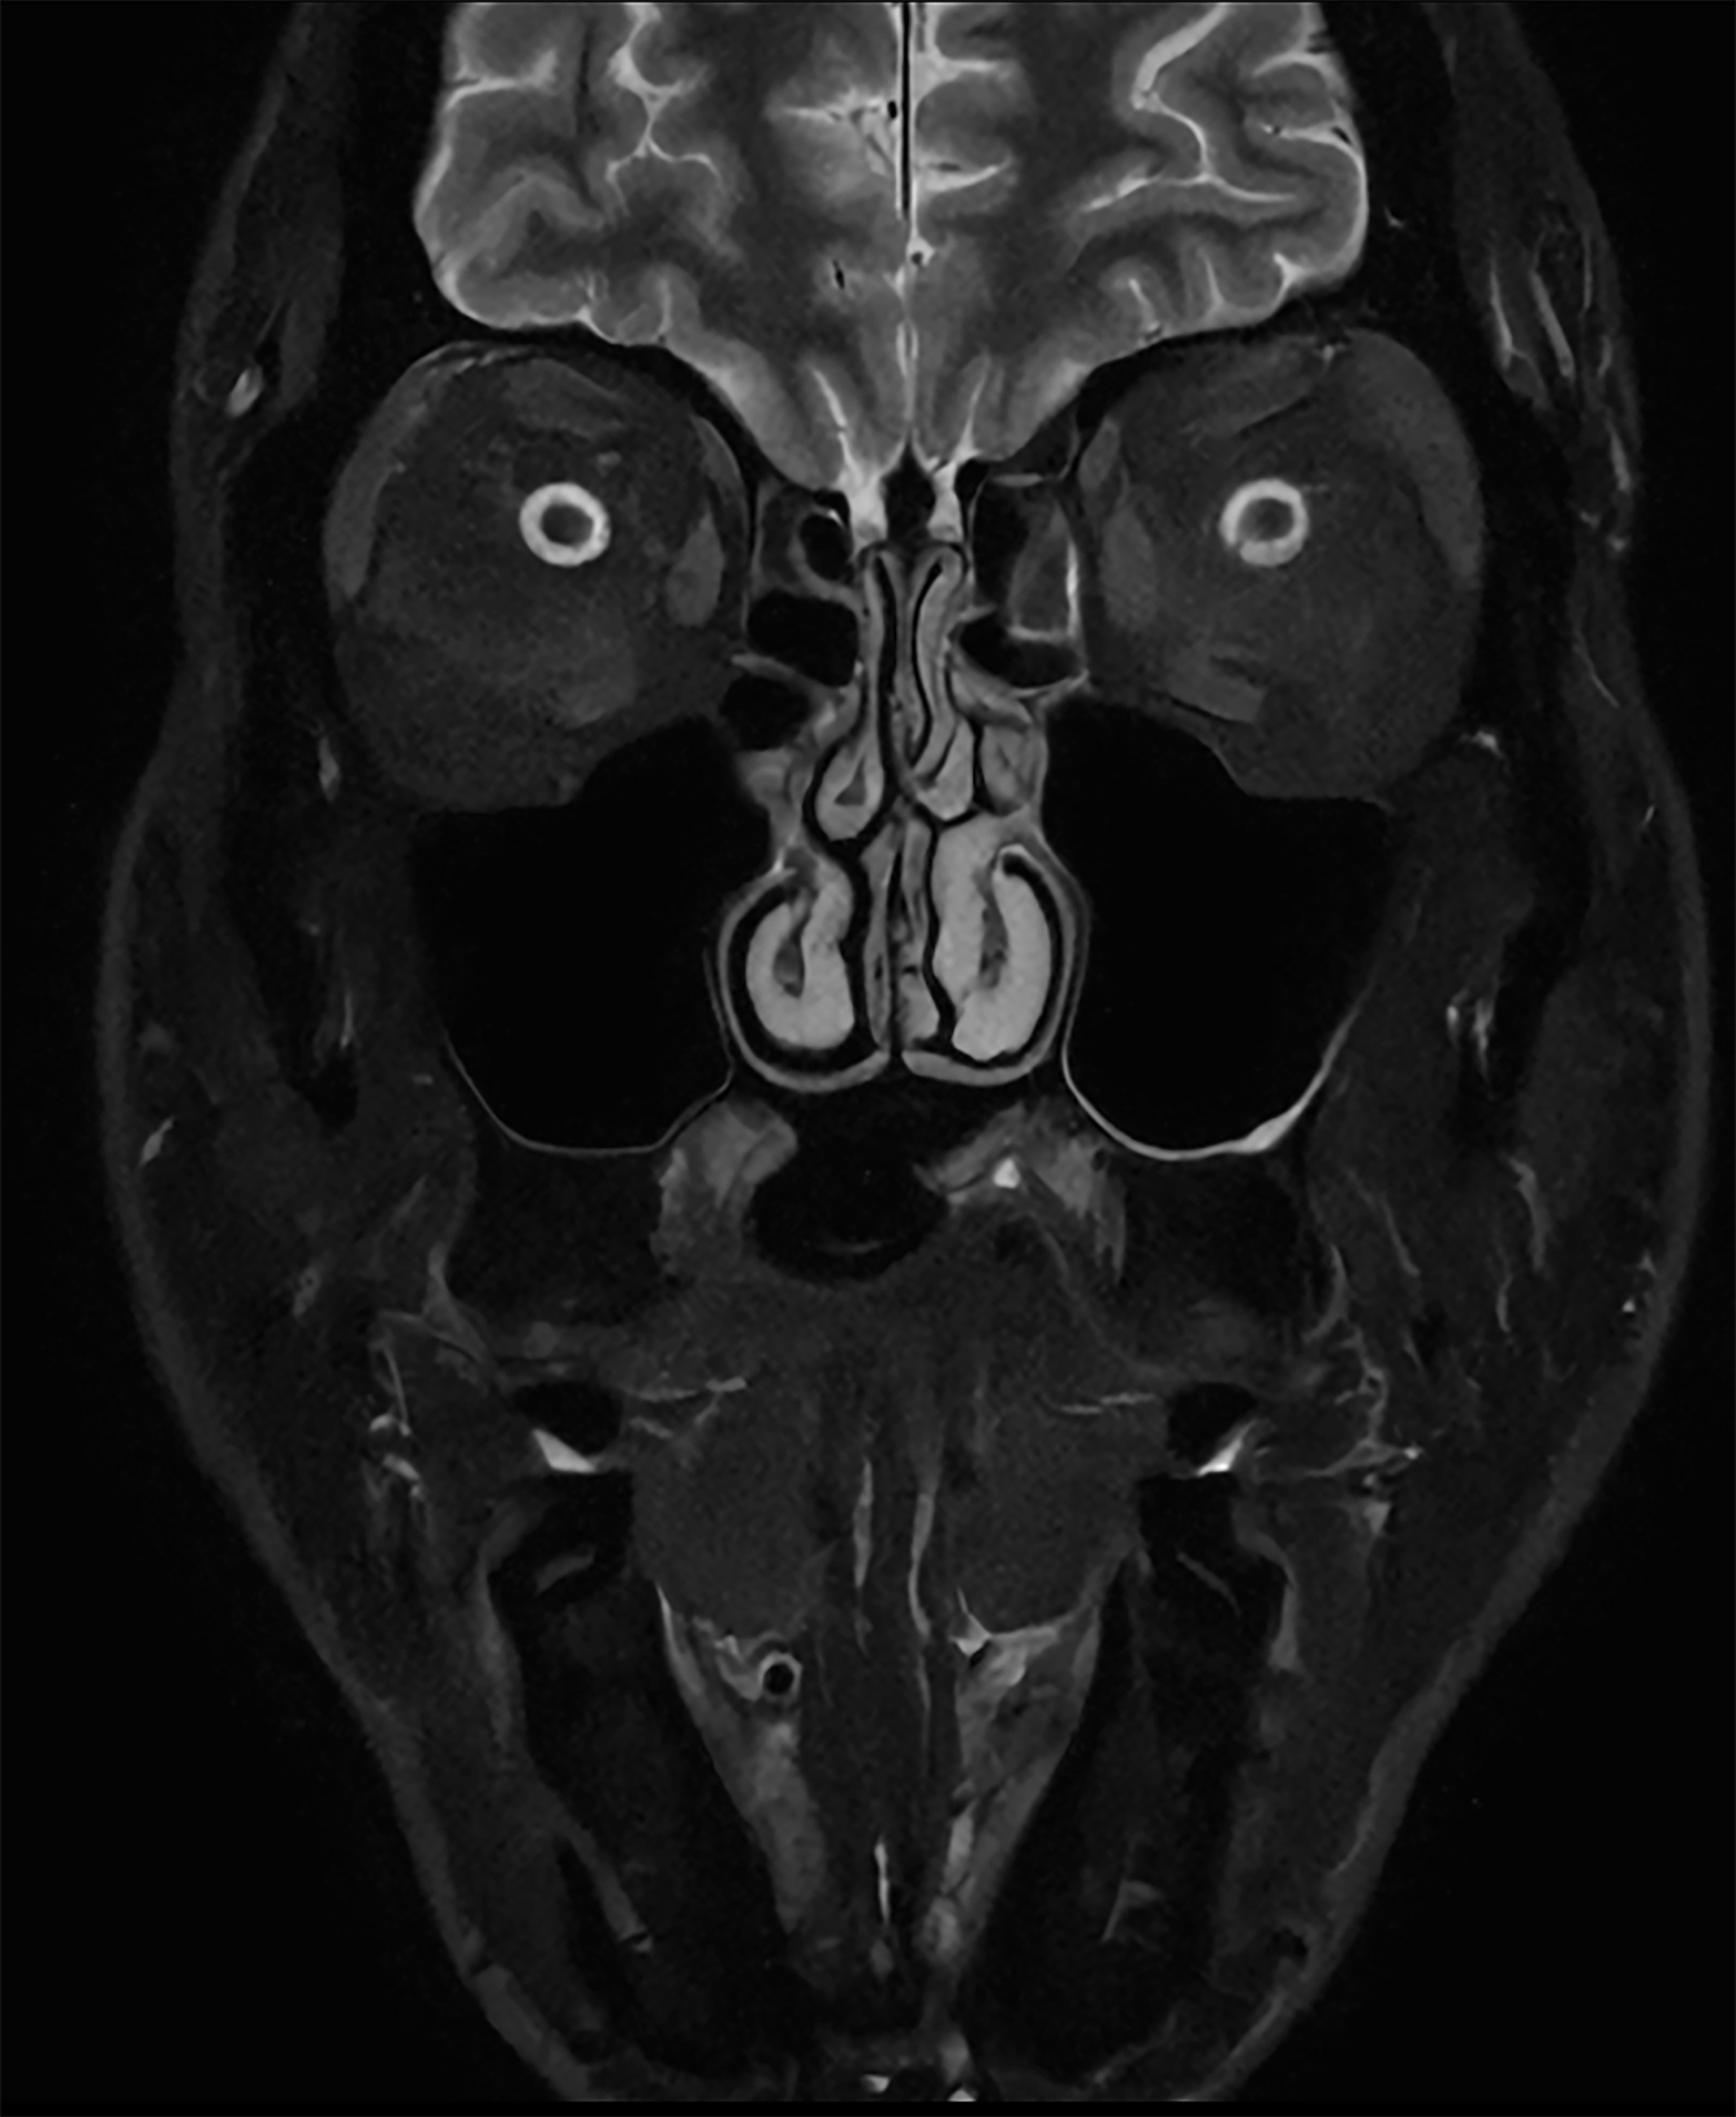

Customers also anticipate significant time savings and workflow improvements with Philips’ dual-AI SmartSpeed Precise [1] technology, which helps streamline their imaging processes, enhance efficiency, and increase patient throughput. “We are impressed by the extremely sharp and crisp images, diagnostic confidence, and fast scans delivered by the dual-AI SmartSpeed Precise solution. We expect it will set a new standard in clinical performance with its ease of use, high image quality, and acceleration controlled by a single parameter,” Picker added.

The latest SmartSpeed Precise [1] technology further enhances productivity, enabling scans to be completed up to three times faster [7], significantly cutting scan times while maintaining exceptional image quality. At the core of SmartSpeed Precise is its dual-AI engine, which delivers an 80% improvement in image sharpness [8], enhancing visualization for more confident and accurate diagnoses. This powerful combination of speed and precision enables radiologists to detect subtle abnormalities with greater clarity, ultimately leading to better patient outcomes. Philips' new release – MR Workspace R12 [6] – introduces a ‘zero-click’ workflow [9], seamlessly guiding the entire imaging process from scan initiation to report generation. By reducing manual intervention and optimizing efficiency, MR Workspace R12 [6] empowers radiology departments to boost patient throughput and reduce backlogs, addressing the increasing demand for faster and more precise imaging. A key innovation within MR Workspace R12 [6] is its AI-powered SmartExam feature, which automates 80% of MR procedures [10], streamlining operations and standardizing imaging workflows.